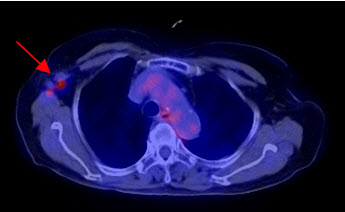

2. Chẩn đoán phân loại giai đoạn hạch nách, xác định giai đoạn bệnh:

Ung thư vú nguyên phát có thể được chia làm hai giai đoạn. Giai đoạn khu trú tại vùng (vú và hạch nách) và giai đoạn di căn xa. Di căn hạch nách là một trong những yếu tố tiên lượng quan trọng nhất giúp các bác sĩ lựa chọn phác đồ điều trị bổ trợ đúng. Nếu không có di căn hạch nách thì không cần thiết phải lấy bỏ hoàn toàn hạch nách, tránh nguy cơ phát triển chứng phù hạch (12%), chứng rối loạn chức năng và sự không thoải mái xảy ra ở hơn 50% những bệnh nhân sau khi vét hạch nách.

Hình 2a: Hình PET toàn thân của bệnh nhân Đỗ Thị N., 87 tuổi. thấy khối u ở vú phải (mũi tên đỏ) và hai hạch nách phải (mũi tên xanh) tăng hấp thu FDG.

Hình 2b: cho thấy rõ mức độ tập trung cao FDG tại vùng có khối u ở vú phải, max SUV=10,24.

Hình 2c: cho thấy hình ảnh hai hạch nách tăng hấp thu FDG (hạch di căn ung thư vú).